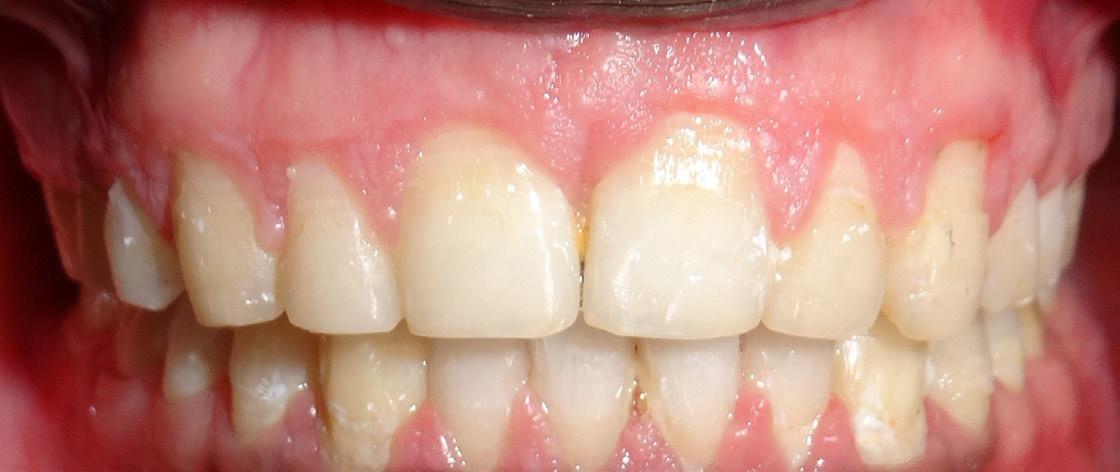

All selfies at T0 and T1 were cropped up to the clavicle of the subject if visible. The backgrounds of the selfies were removed and turned white with the help of Adobe Photoshop CC 2020 version 21.1 software package (Adobe Systems, San Jose, CA). One example of pre-treatment and post-treatment selfies of a subject in skeletal class I is illustrated in Figure 1A and 1B, in skeletal

Figure 1: Skeletal Class I Group (SCI) Male.

A-Pre-treatment (T0) Selfie; B- Post-treatment (T1) Selfie; C. Pretreatment Profile Silhouette (T0). D. Post-treatment Profile Silhouette

class II is illustrated in Figure 2A and 2B, and in skeletal class III is illustrated in Figures 3A and 3B.